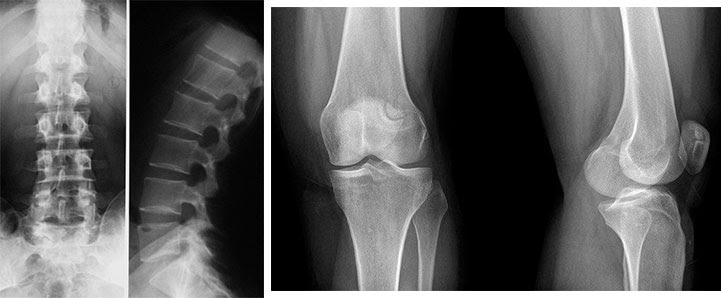

Obavili su kompletan pregled, uradili testove, slikali me , lekar (starija žena) mi je dijagnostikovala artritis, artrozu i osteohondrozu kičme, pokazala mi rendgenske snimke i rezultate opšteg pregleda. Odmah sam se setio svoje svekrve, jer je i ona imala dijagnozu pre 6 godina, a 6 godina se kretala u invalidskim kolicima, uplašio sam se! Što se tiče osteohondroze leđa u mojoj fazi, rekla je da ako se ništa ne preduzme, može zakrčiti živce u leđima, tako da delovi tela mogu početi da propadaju, pošto kod osteohondroze zglobovi se deformišu i mogu da vam stisnu živce, rekla je i ako ne lečim artritis i artrozu, onda takođe Mogu postati osoba sa invaliditetom bez nogu, ukratko, puni PPC, da budem iskrena, ne mogu preneti svoje stanje u tom trenutku, i što je najvažnije, sećam se kako je rekla: „Sa godinama, rizik od artritisa se samo povećava, pa prevenciju treba započeti od mladosti, šta je sa tim? nisam znao?" Da budem iskren, bio sam bez slike iz ove situacije! Pokušala me je nagovoriti na operaciju, kaže da nema drugog izlaza. Operacija je bila jako skupa, a osim toga, nisam mlad, hoću li se oporaviti nakon takve operacije, pomislio sam.